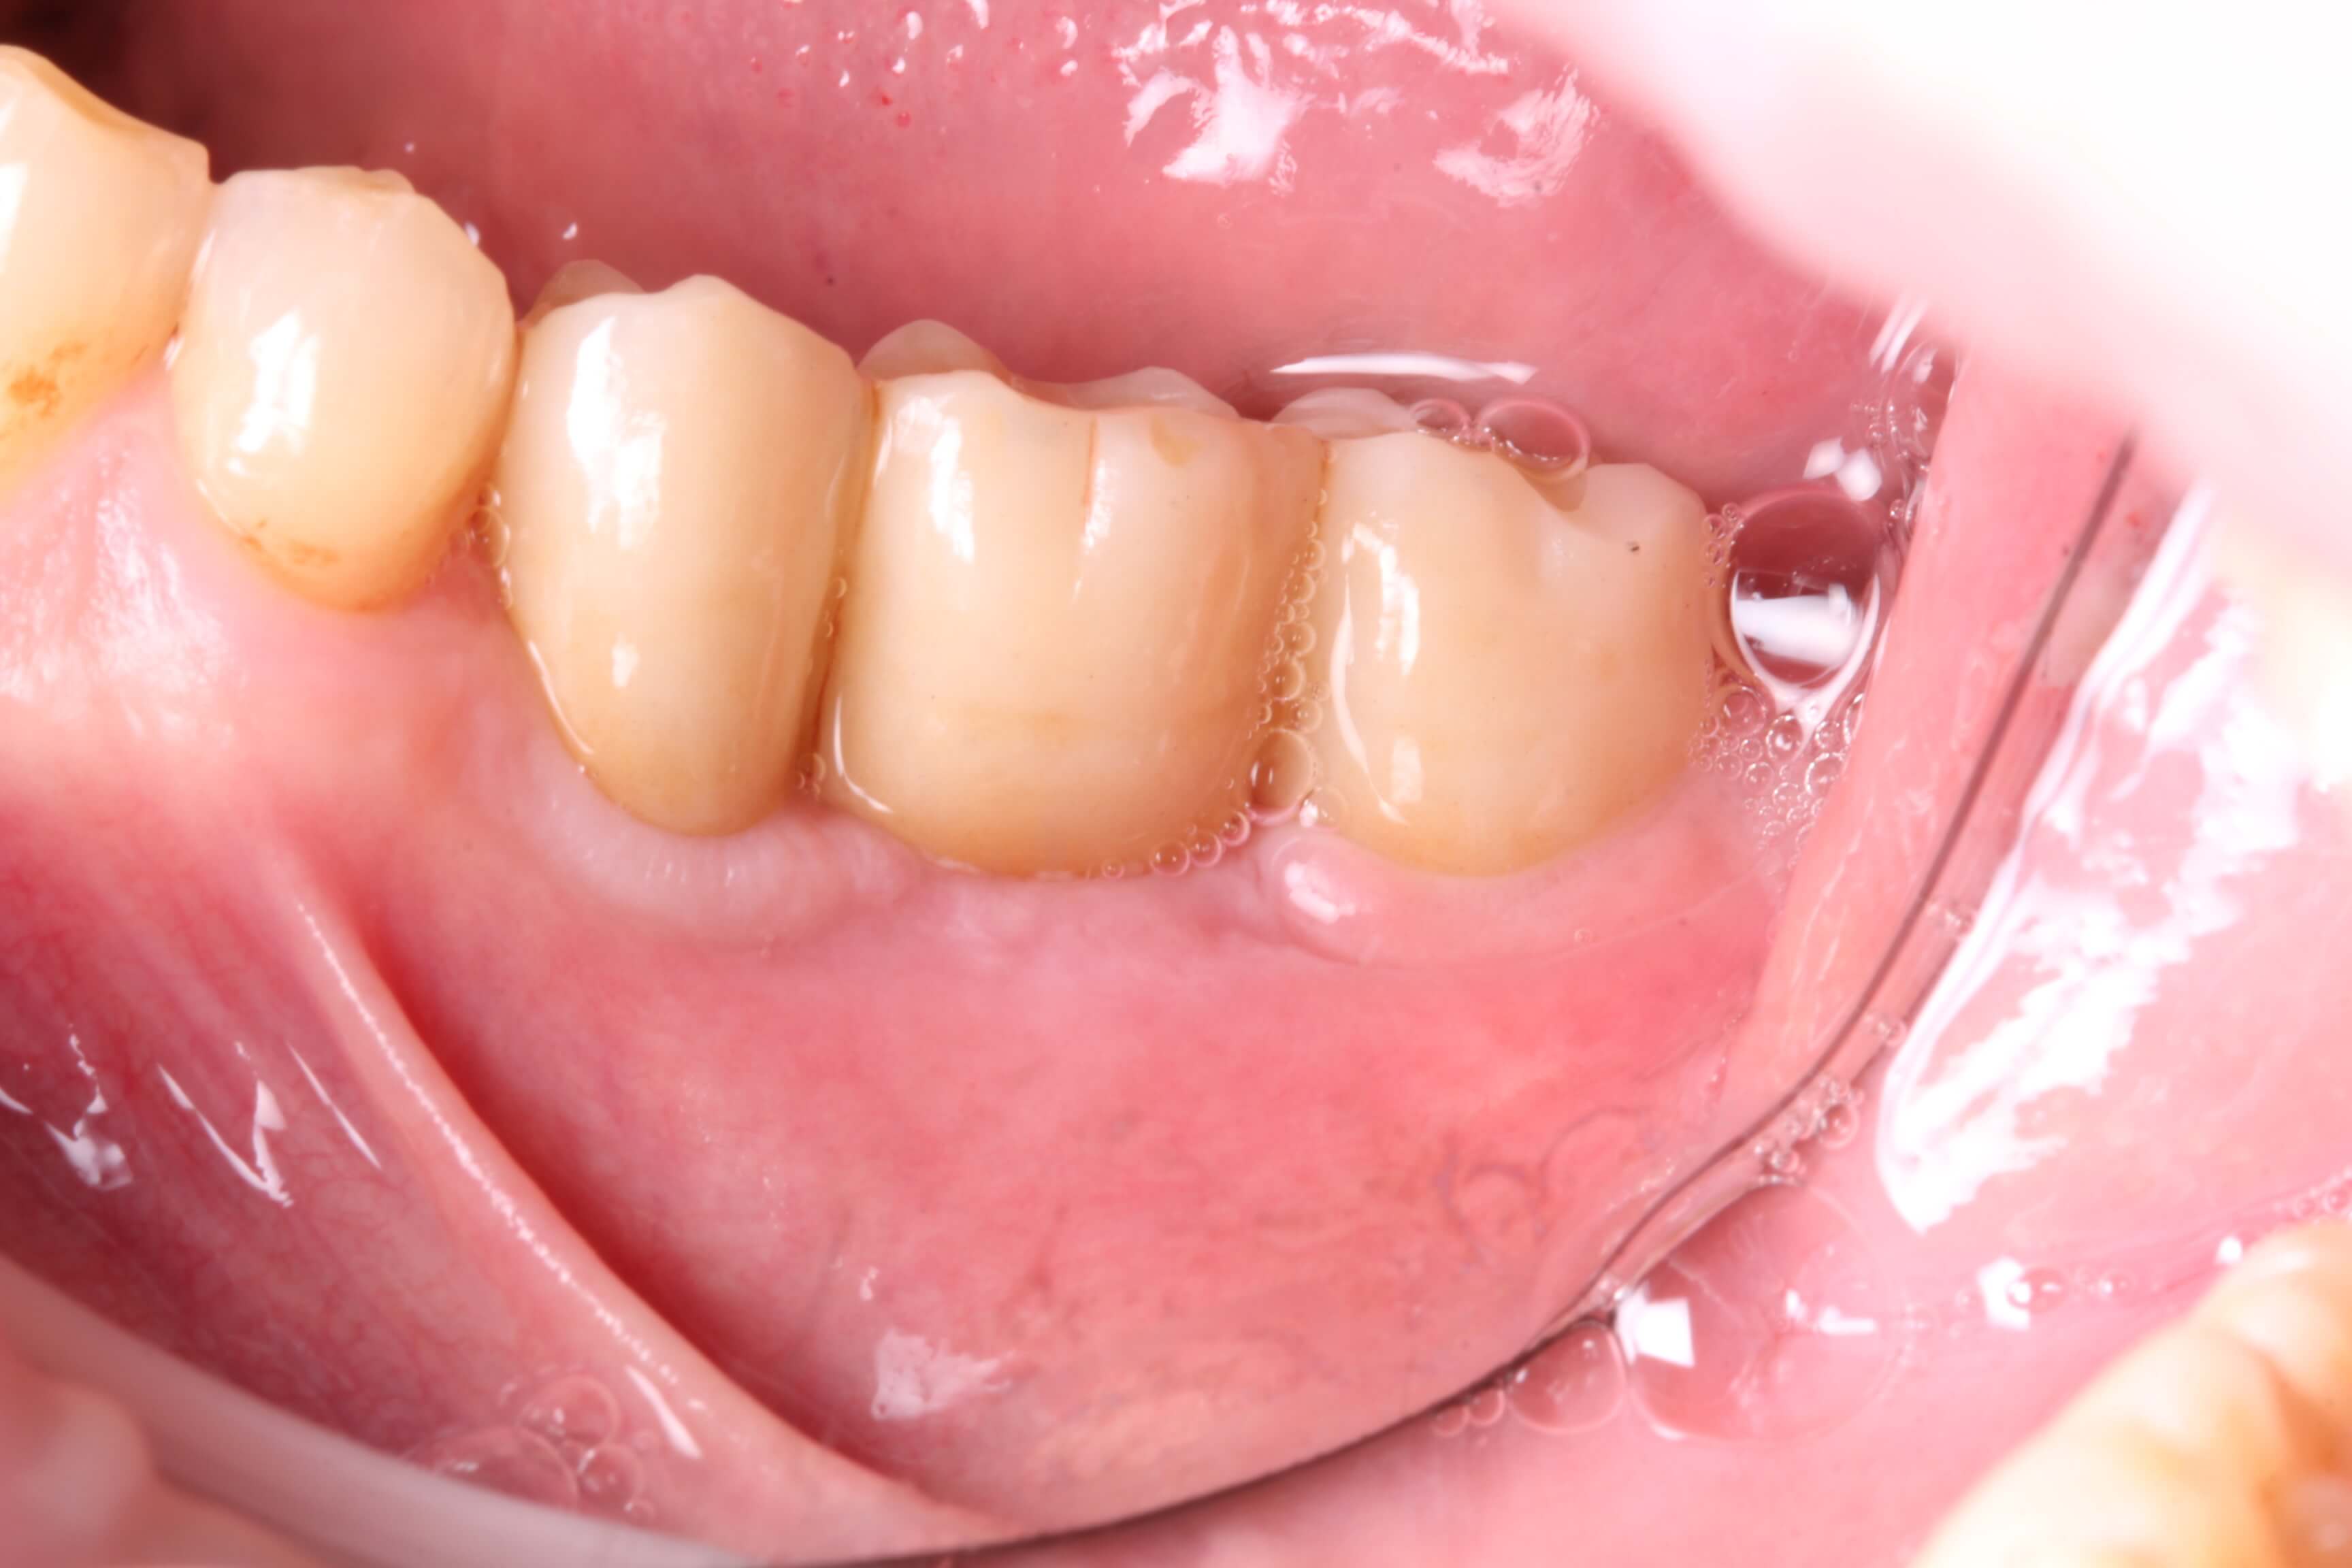

Ровно через 4 месяца было проведено протезирование боковых отделов циркониевыми коронками, а также мостовидными протезами с опорой на имплантатах.